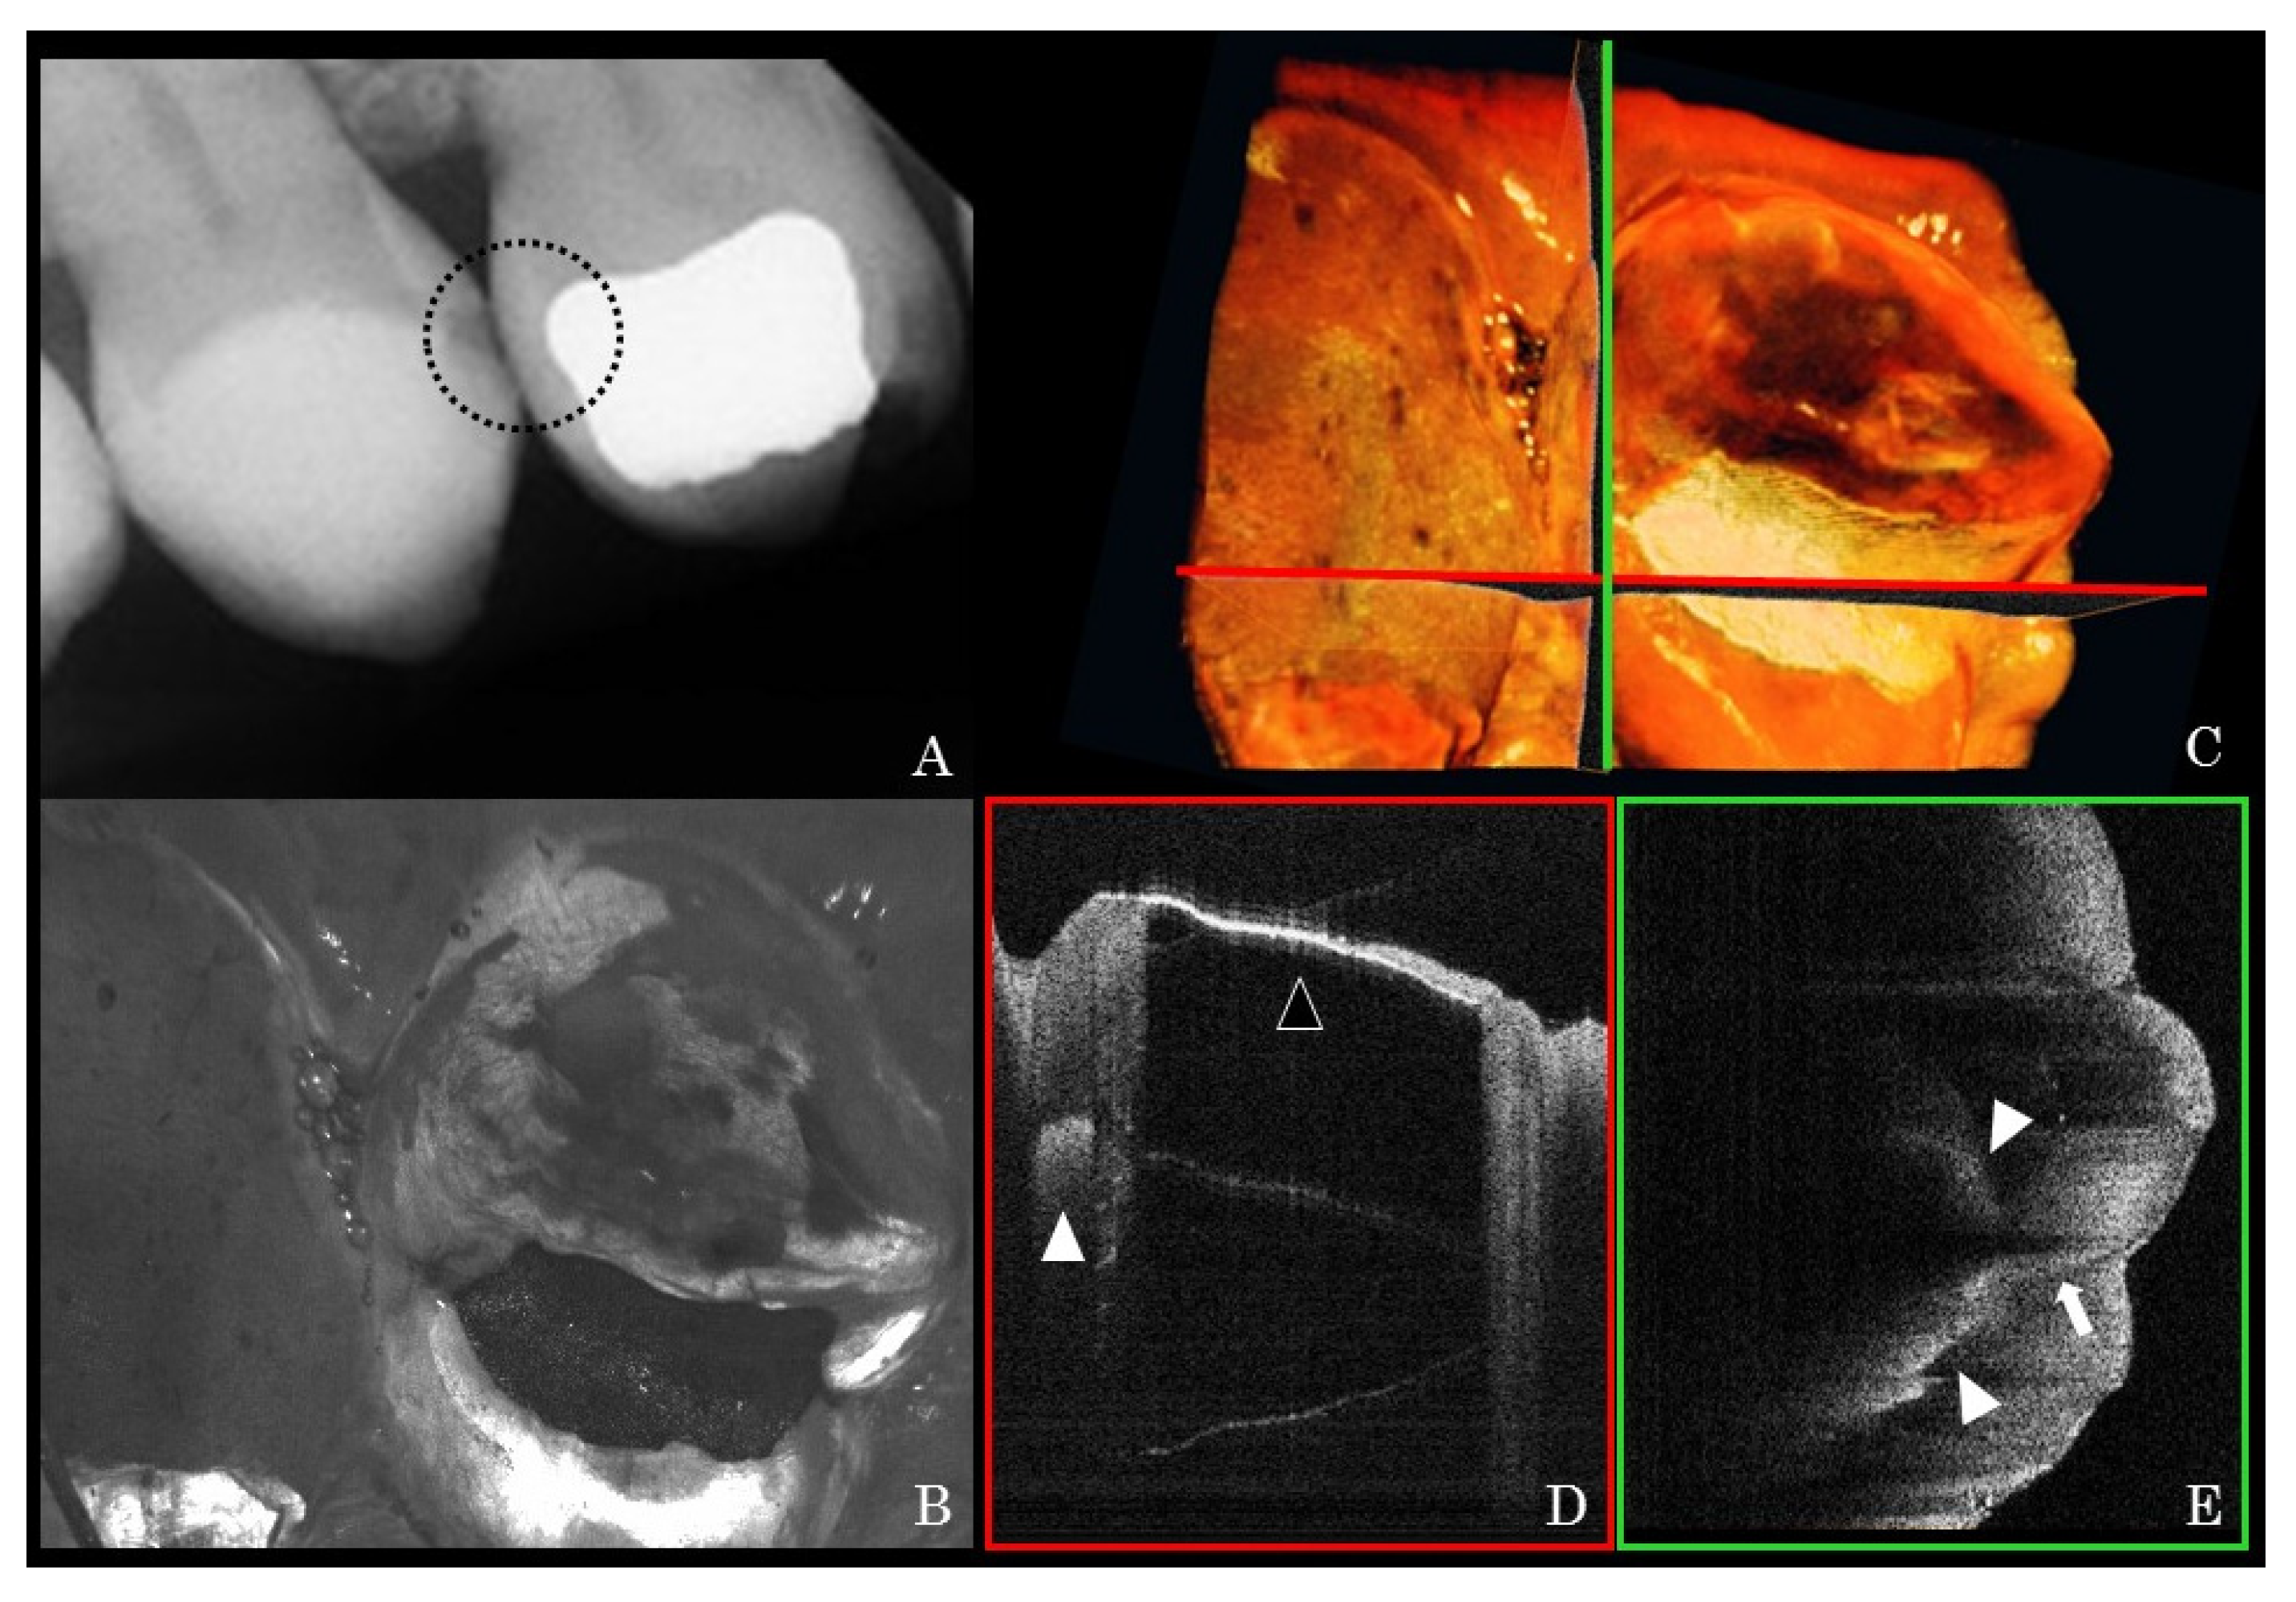

- Shimada, Y.; Sadr, A.; Sumi, Y.; Tagami, J. Application of Optical Coherence Tomography (OCT) for Diagnosis of Caries, Cracks, and Defects of Restorations. Curr. Oral Health Rep. 2015, 2, 73–80. [Google Scholar] [CrossRef] [Green Version]

- Luong, M.N.; Shimada, Y.; Araki, K.; Yoshiyama, M.; Tagami, J.; Sadr, A. Diagnosis of Occlusal Caries with Dynamic Slicing of 3D Optical Coherence Tomography Images. Sensors 2020, 20, 1659. [Google Scholar] [CrossRef] [Green Version]

- Shimada, Y.; Nakagawa, H.; Sadr, A.; Wada, I.; Nakajima, M.; Nikaido, T.; Otsuki, M.; Tagami, J.; Sumi, Y. Noninvasive cross-sectional imaging of proximal caries using swept-source optical coherence tomography (SS-OCT) in vivo. J. Biophotonics 2014, 7, 506–513. [Google Scholar] [CrossRef]